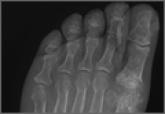

Emergency Imaging: Right hallux pain

- Author:

- Keith D. Hentel, MD, MS